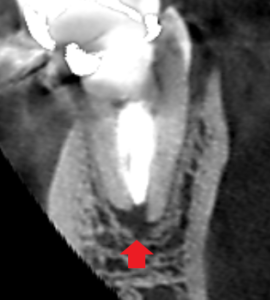

下顎大臼歯遠心根の冠状断のCT画像です。

赤い矢印の先に膿の影がみられます。根尖孔が大きく、

根の先まで根管充填で封鎖するのが難しいケースです。